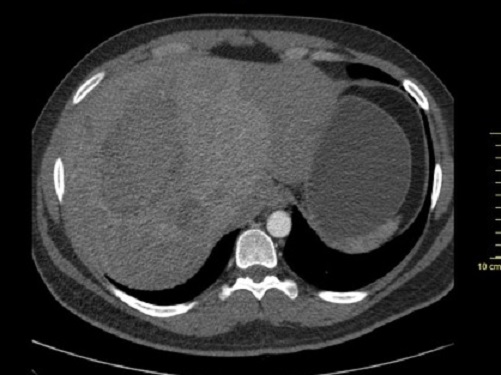

Image de kytes

multiple tres volumineuse du foie droit et a lobe gauche du

foie. Ce sont des image ovalaire hypodensite a

bord tres nette , bien limite situe au foie droit |

Aspect TDM une

kyste du foie droit avec image de calcifie

de sa paroi . En cas hemorragie

intrakystique on peut en voyait image de cailleaux

hyperdense du sang |